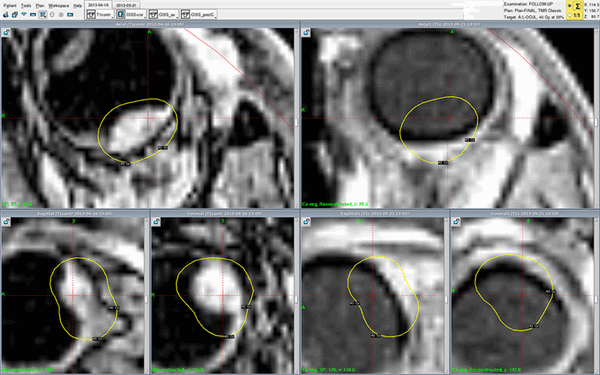

Пример установки радиоактивного аппликатора для лечения меланомы радужки

Реальный клинический случай - лечение меланомы хориоидеи Гамма-ножом Gamma-Knife Perfexion в Онкологической клинике МИБС. Снимки МРТ с контрастом (слева - до, справа - после лечения). Меланома хориоидеи на правом снимке, сделанном во время контрольного обследования всего через один месяц (!), не визуализируется - желтые контуры изначального расположения опухоли нанесены для сравнения. Опухоль исчезла. Без операции, с сохранением глазного яблока.